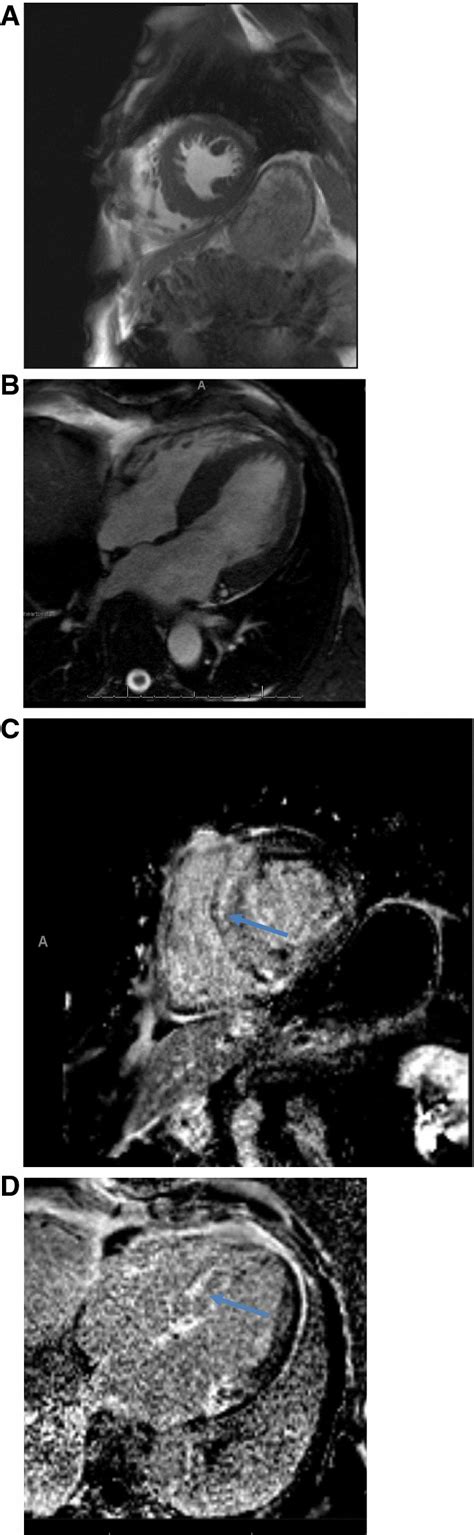

MRI Scans: Soft Tissue Details

Magnetic Resonance Imaging (MRI) is excellent for visualizing soft tissues and can sometimes offer a better view than CT for specific situations. For mesothelioma, an MRI might be used to assess if the tumor has invaded the diaphragm, chest wall, or spinal cord. It helps in distinguishing between benign and malignant pleural thickening in some cases, though a biopsy remains the gold standard.